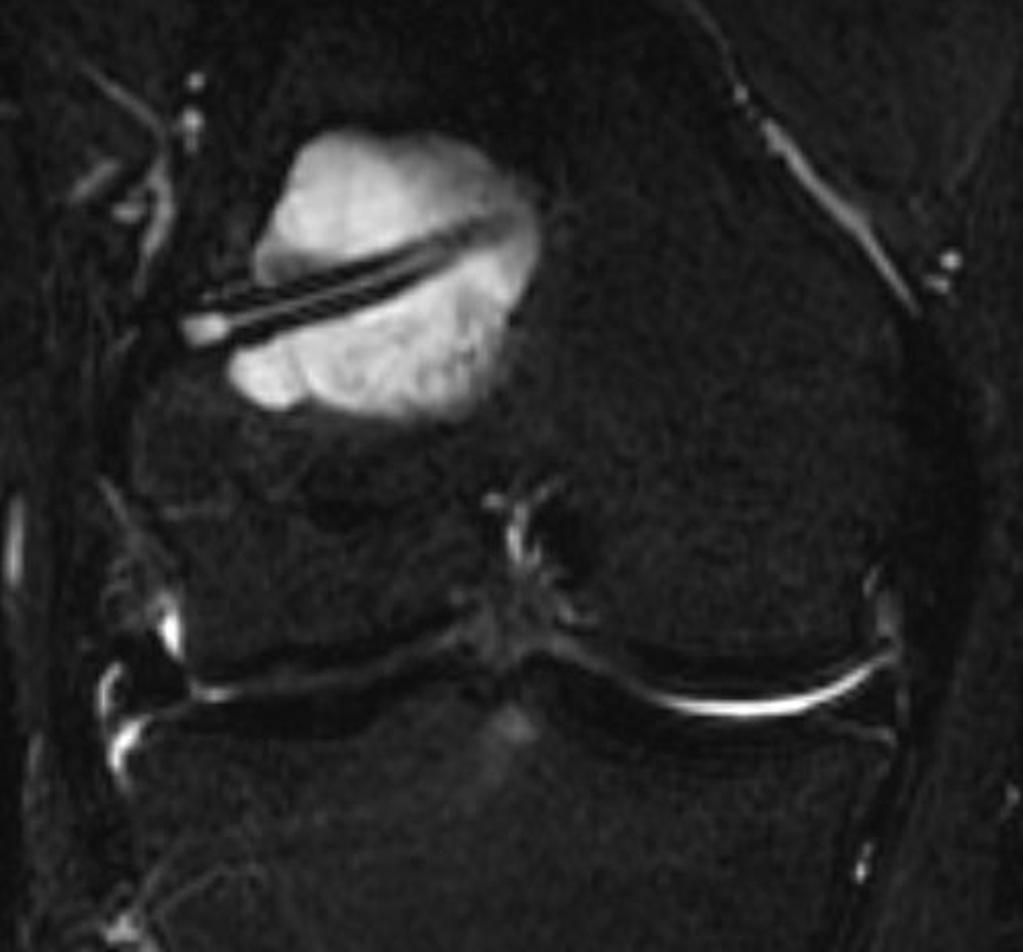

Dégénérescence kystique de la plastie à l’intérieur des tunnels

Case courtesy of Dr Roberto Schubert, Radiopaedia.org. From the case Femoral tunnel cyst after ACL graft reconstruction